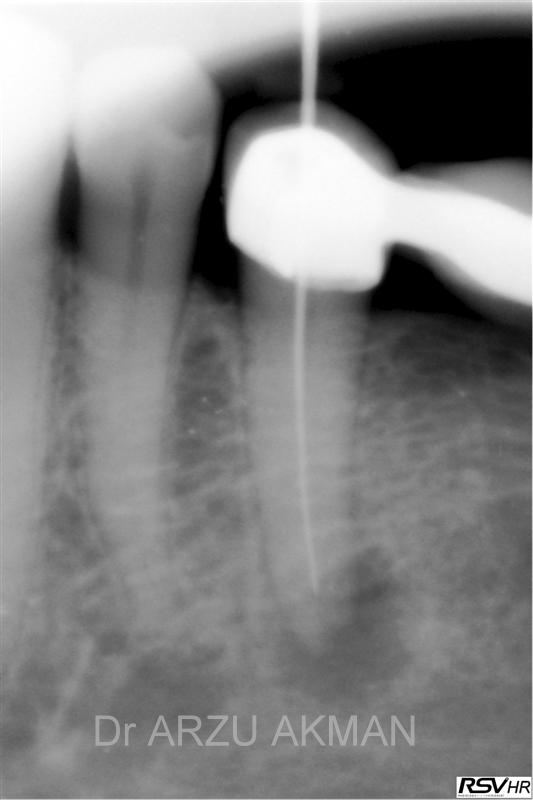

Aşağıdaki vakada daha önce kanal tedavisi yapılmış bir dişin içinde alet kırılması nedeni ile ,kanalın tam doldurulamadığı ve kök ucunda kist oluştuğu görülüyor. Öncesinde çekilmesine karar verilmiş bu vakada uygun aletlerle kırık aletin yanından geçilerek(by-pass), eski kanal dolgusu sökülerek döner aletler ve lazer eşliğinde yeni kanal dolgusu yapıabilmektedir .(retreatment)